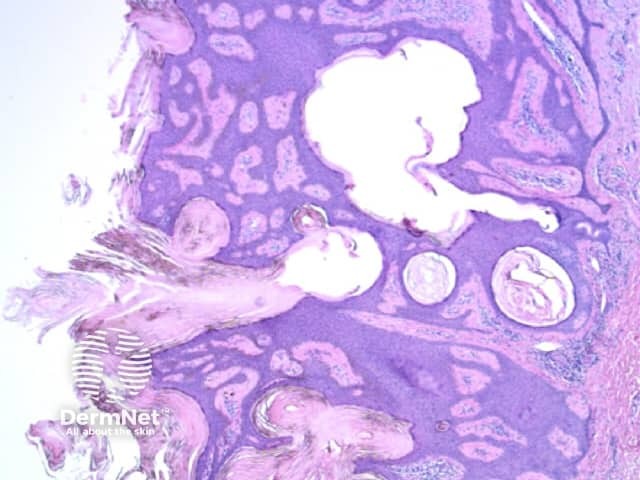

Seborrhoeic keratoses are amongst the most variable lesions on dermatoscopy, which is reflected in their protean histological appearances (Figure 15). Aside from the pseudopod pattern, any pattern or colour can be found. Flat seborrhoeic keratoses appear similar to solar lentigo on dermatoscopy. With early epidermal acanthosis thin curved lines (Figure 13) and circles become manifest, whilst with advanced acanthosis thick curved lines (Figure 14) and clods typically predominate. White clods are due to keratin under the stratum corneum. Orthokeratotic loosely laminated surface keratin appears yellow. Crypts fill with discoloured keratin and may appear various colours on dermatoscopy including brown and orange (Figure 15).

Figure 13 Figure 14 Figure 15

Figure 15a Figure 15b Figure 15c